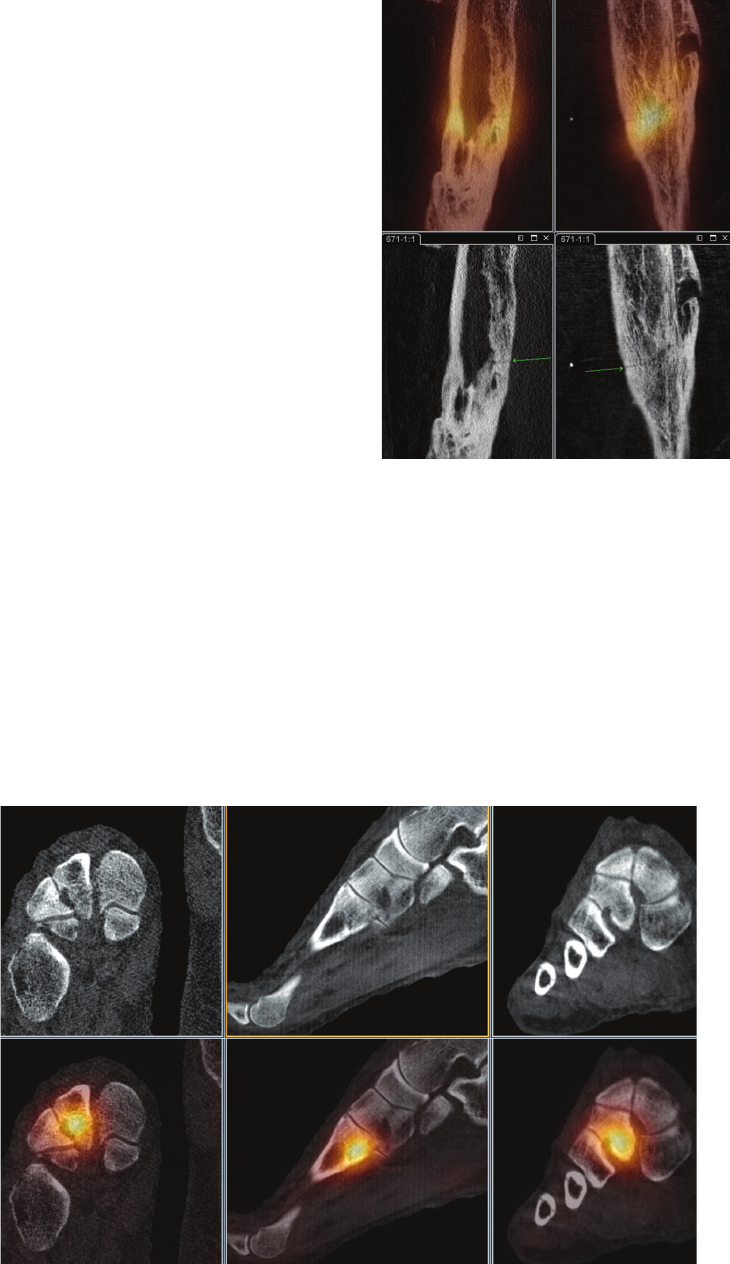

Figure 11 is an example where BrightView XCT provided

information that allowed more aggressive orthopedic

treatment with subsequent good outcome, while Figure

12 is a case that demonstrates that the quality of the

high-resolution CT images provided by BrightView XCT

can obviate the need for additional imaging studies, and

Figure 13 is an example where these high-resolution CT

images were used to plan a surgical intervention.

Figure 10 Tc-99m HDP SPECT/CT study of a 64-year-old female with right midfoot pain for one week.

BrightView XCT study was performed when no evidence of fracture was observed on radiographs.

SPECT/CT study revealed acute fracture of base of second right metatarsal.

Clinical data courtesy of Sutherland Nuclear Medicine, Sydney, Australia

Figure 11 Tc-99m MDP SPECT/CT study performed on a 22-year-old male

12 weeks post scaphoid fracture due to continued tenderness. BrightView XCT

study conrmed scaphoid fracture with incomplete union. After more

aggressive orthopedic treatment, fracture healed and patient is symptom-free.

Clinical data courtesy of The Royal Wolverhampton Hospitals NHS Trust, Surrey, UK

Figure 12 Tc-99m HPD SPECT/CT study performed on a patient with

right heel pain for a few months. BrightView XCT study revealed intense

uptake in right calcaneus along a fracture line posteriorly in the CT, which also

demonstrated malalignment and impaction of the fracture. Patient was managed

appropriately for the stress fracture and orthopedic review was arranged to

assess the malalignment of the fracture. No further imaging was required.

Clinical data courtesy of Sydney X-Ray, Sydney, Australia

Figure 15 Tc-99m HDP SPECT/CT study of a 43-year-old female patient with

right foot pain, status post trauma. BrightView XCT study was performed to

assess for possible fracture. SPECT images revealed multiple foci (at least three)

of activity within the mid-portion of the right foot that correlated to the joint

spaces on CT images. No evidence of fracture or activity correlated to bony

structures was observed.

Clinical data courtesy of Washington Hospital Center, Washington, DC